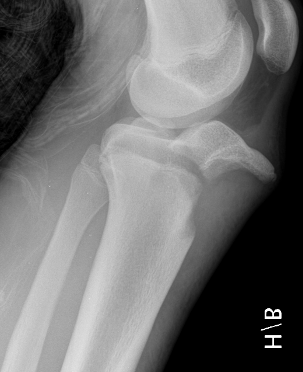

Ogden Classification

A: Undisplaced

B: Displaced

| Type I | Type II | Type III | Type IV |

|---|---|---|---|

| Avulsion distal tibial tubercle | Extension into tibial physis but not into knee joint | Extension across tibial physis and into knee joint | Extends posteriorly across tibial physis |

| Disrupts extensor mechanism | Disrupts extensor mechanism |

Disrupts extensor mechanism Disrupts articular surface Disrupts growth plate |

|

Associated Osgood-Schlatter Second most common |

Most common Risk of compartment syndrome |

Risk of compartment syndrome |